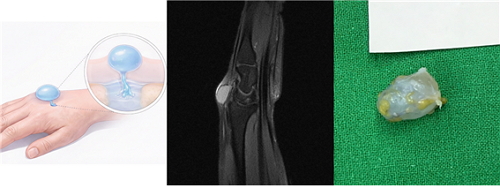

¼Õ¸ñ °áÀýÁ¾ ¸ð½Äµµ(ÁÂ), ¼Õ¸ñ °áÀýÁ¾ MRI(Áß°£), Á¦°ÅµÈ °áÀýÁ¾(¿ì)

(ÀÚ·áÁ¦°ø: ÀÇÁ¤ºÎ ¿¬¼¼º£½ºÆ®º´¿ø Àåö¿µ º´¿øÀå)